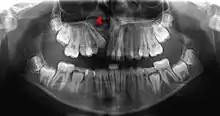

This X-ray film reveals some bone loss on the right side of the mandible. The associated teeth exhibit poor crown-to-root ratios and may be subject to secondary occlusal trauma.

Bone is lost through the process of resorption which involves osteoclasts breaking down the hard tissue of bone. A key indication of resorption is when scalloped erosion occurs. This is also known as Howship's lacuna.[18] The resorption phase lasts as long as the lifespan of the osteoclast which is around 8 to 10 days. After this resorption phase, the osteoclast can continue resorbing surfaces in another cycle or carry out apoptosis. A repair phase follows the resorption phase which lasts over 3 months. In patients with periodontal disease, inflammation lasts longer and during the repair phase, resorption may override any bone formation. This results in a net loss of alveolar bone.[19]

Alveolar bone loss is closely associated with periodontal disease. Periodontal disease is the inflammation of the gums. Studies in osteoimmunology have proposed 2 models for alveolar bone loss. One model states that inflammation is triggered by a periodontal pathogen which activates the acquired immune system to inhibit bone coupling by limiting new bone formation after resorption.[20] Another model states that cytokinesis may inhibit the differentiation of osteoblasts from their precursors, therefore limiting bone formation. This results in a net loss of alveolar bone.[21]